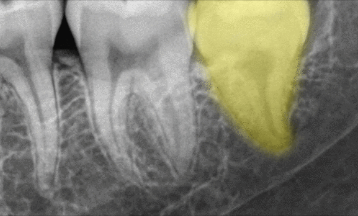

치근단 사진에서도 심한 골흡수 양상이 나타나,

빠른 발치가 필요하다고 판단하게 되었습니다.

그러나 아래 앞니가 없다면

일상 생활 중 많은 불편을 느끼며

다른 부위에도 복합적인 문제가

생길 수 있습니다.